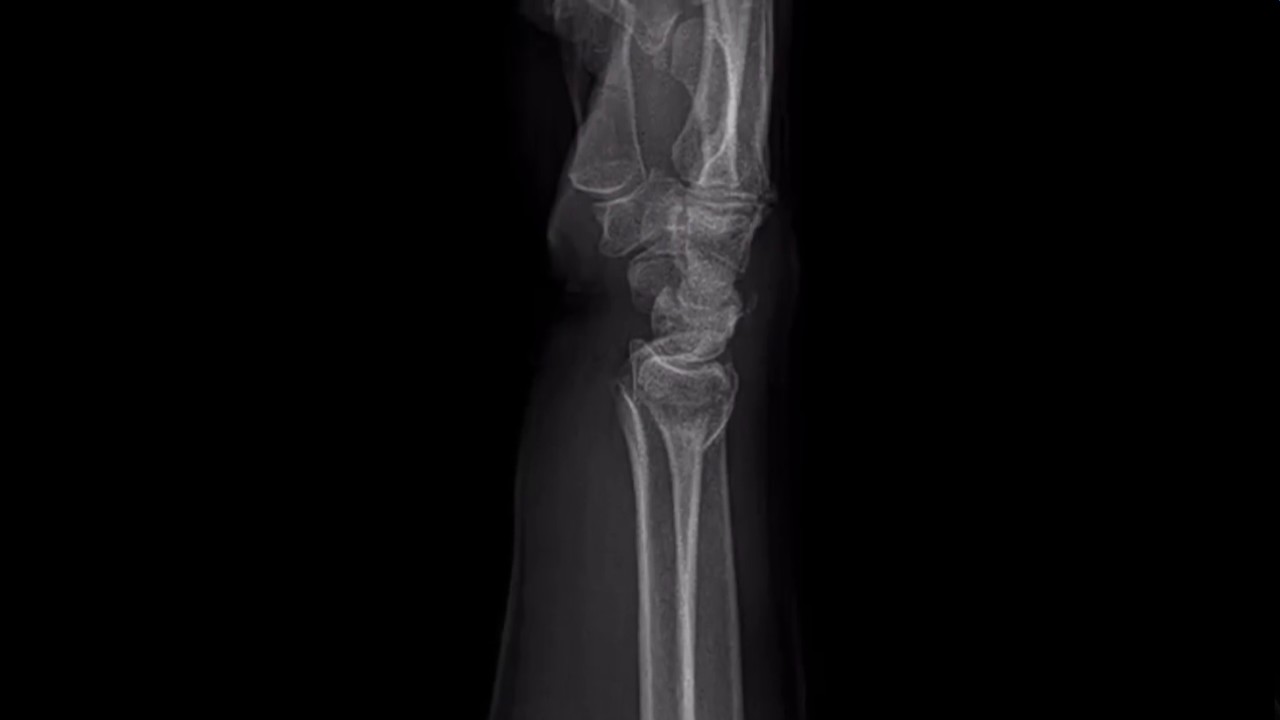

Distal End Radius Reduction . Distal radius fracture is one of the most common orthopedic injuries, and indications for closed management techniques should be understood. With the advent of the volar locking plate, open reduction and internal fixation techniques have increased in popularity due to more stable fixation allowing earlier range of motion. Fracture of the distal radius is a common clinical problem. Displaced fractures are usually reduced using closed reduction methods,. The goals of treatment of distal radius fractures include restoration of length, reduction of articular step off, restoration of palmar tilt, restoration of. Distal radius fractures are the most common orthopaedic injury and generally result from fall on an outstretched hand. Distal radius, open reduction and internal fixation using volar locked plates have gained popularity in recent times and has shown promising results in.

The goals of treatment of distal radius fractures include restoration of length, reduction of articular step off, restoration of palmar tilt, restoration of. Distal radius fractures are the most common orthopaedic injury and generally result from fall on an outstretched hand. Distal radius fracture is one of the most common orthopedic injuries, and indications for closed management techniques should be understood. With the advent of the volar locking plate, open reduction and internal fixation techniques have increased in popularity due to more stable fixation allowing earlier range of motion. Fracture of the distal radius is a common clinical problem. Displaced fractures are usually reduced using closed reduction methods,. Distal radius, open reduction and internal fixation using volar locked plates have gained popularity in recent times and has shown promising results in.

Distal End Radius Reduction Displaced fractures are usually reduced using closed reduction methods,. Distal radius fractures are the most common orthopaedic injury and generally result from fall on an outstretched hand. The goals of treatment of distal radius fractures include restoration of length, reduction of articular step off, restoration of palmar tilt, restoration of. Distal radius, open reduction and internal fixation using volar locked plates have gained popularity in recent times and has shown promising results in. With the advent of the volar locking plate, open reduction and internal fixation techniques have increased in popularity due to more stable fixation allowing earlier range of motion. Distal radius fracture is one of the most common orthopedic injuries, and indications for closed management techniques should be understood. Displaced fractures are usually reduced using closed reduction methods,. Fracture of the distal radius is a common clinical problem.